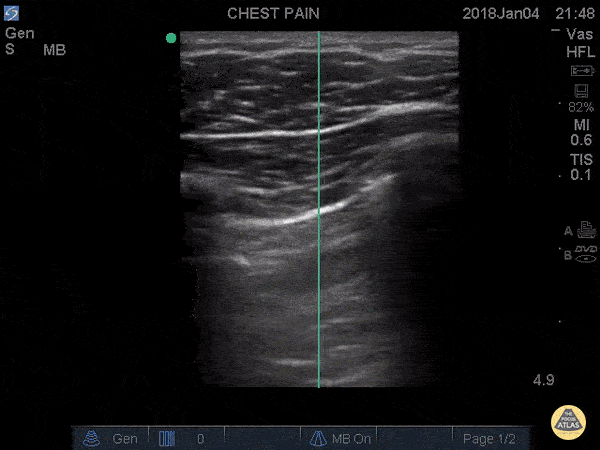

Normal lung sliding appears and disappears with the patients breath revealing an area without lung slide. Move up one rib space to the apex, and theres no lung slide at all. This image is from the actual case described. - Dr. Matthew Riscinti - The POCUS Atlas and Kings County Emergency Medicine